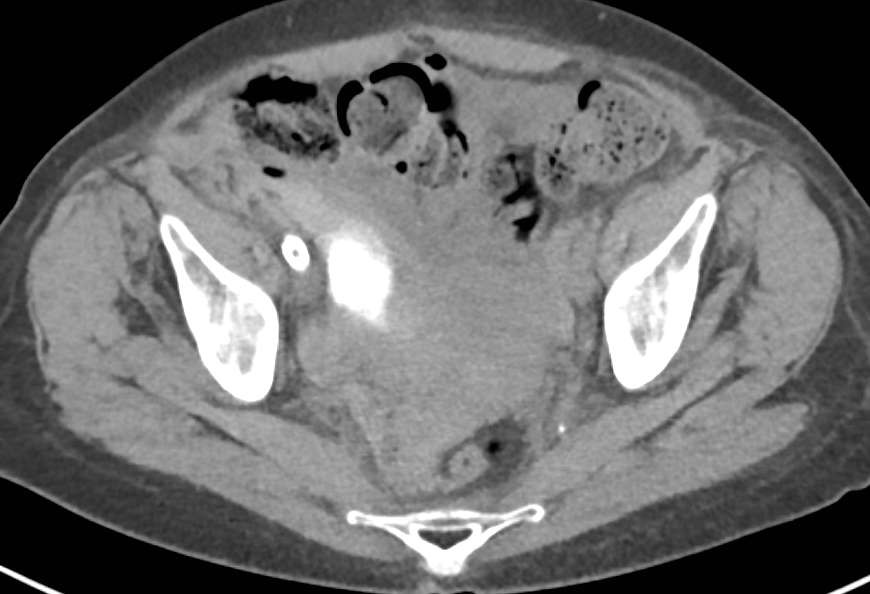

穿刺点过高导致盆腔内血肿